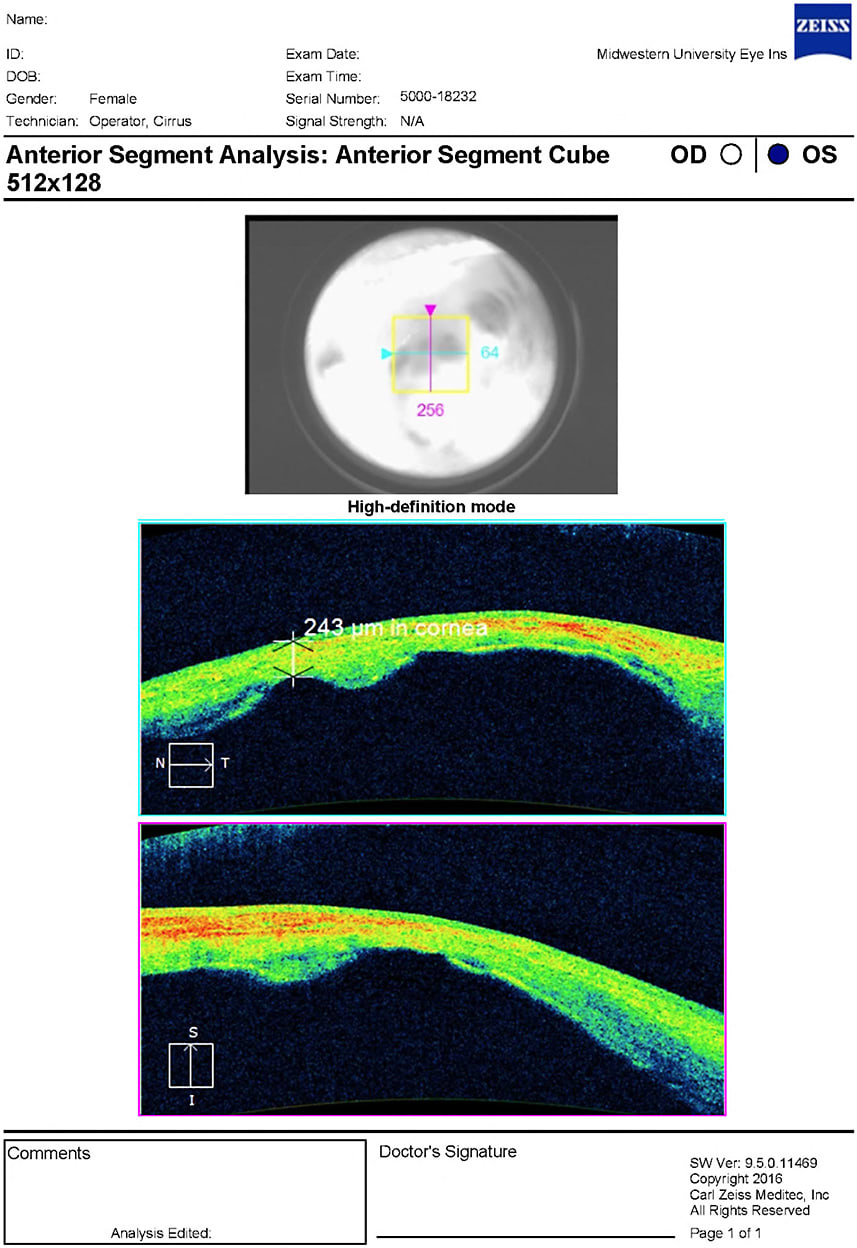

Figures 1 and 2 show the patient in primary and downgaze, respectively. Figures 3 and 4 demonstrate the corneal staphyloma using anterior segment optical coherence tomography. This patient was diagnosed with corneal staphyloma and minor scleromalacia secondary to surgical complications from fetal alcohol syndrome. She deferred enucleation and/or ocular prosthetic consult.

All testing for OD revealed normal findings with 20/20 uncorrected visual acuity. OS had no light perception with 4+ afferent pupillary defect (APD). Severe vascularized opacification was found on the OS cornea with multiple areas of elevation and uveal show. A tube shunt was observed superior nasally, but unable to assess patency. The intraocular pressure was 13 mmHg and 20 mmHg for OD and OS, respectively. Dilated fundus examination for OS was not able to be viewed. B-scan ultrasonography was performed and found vitreous degeneration with a grossly flat retina.